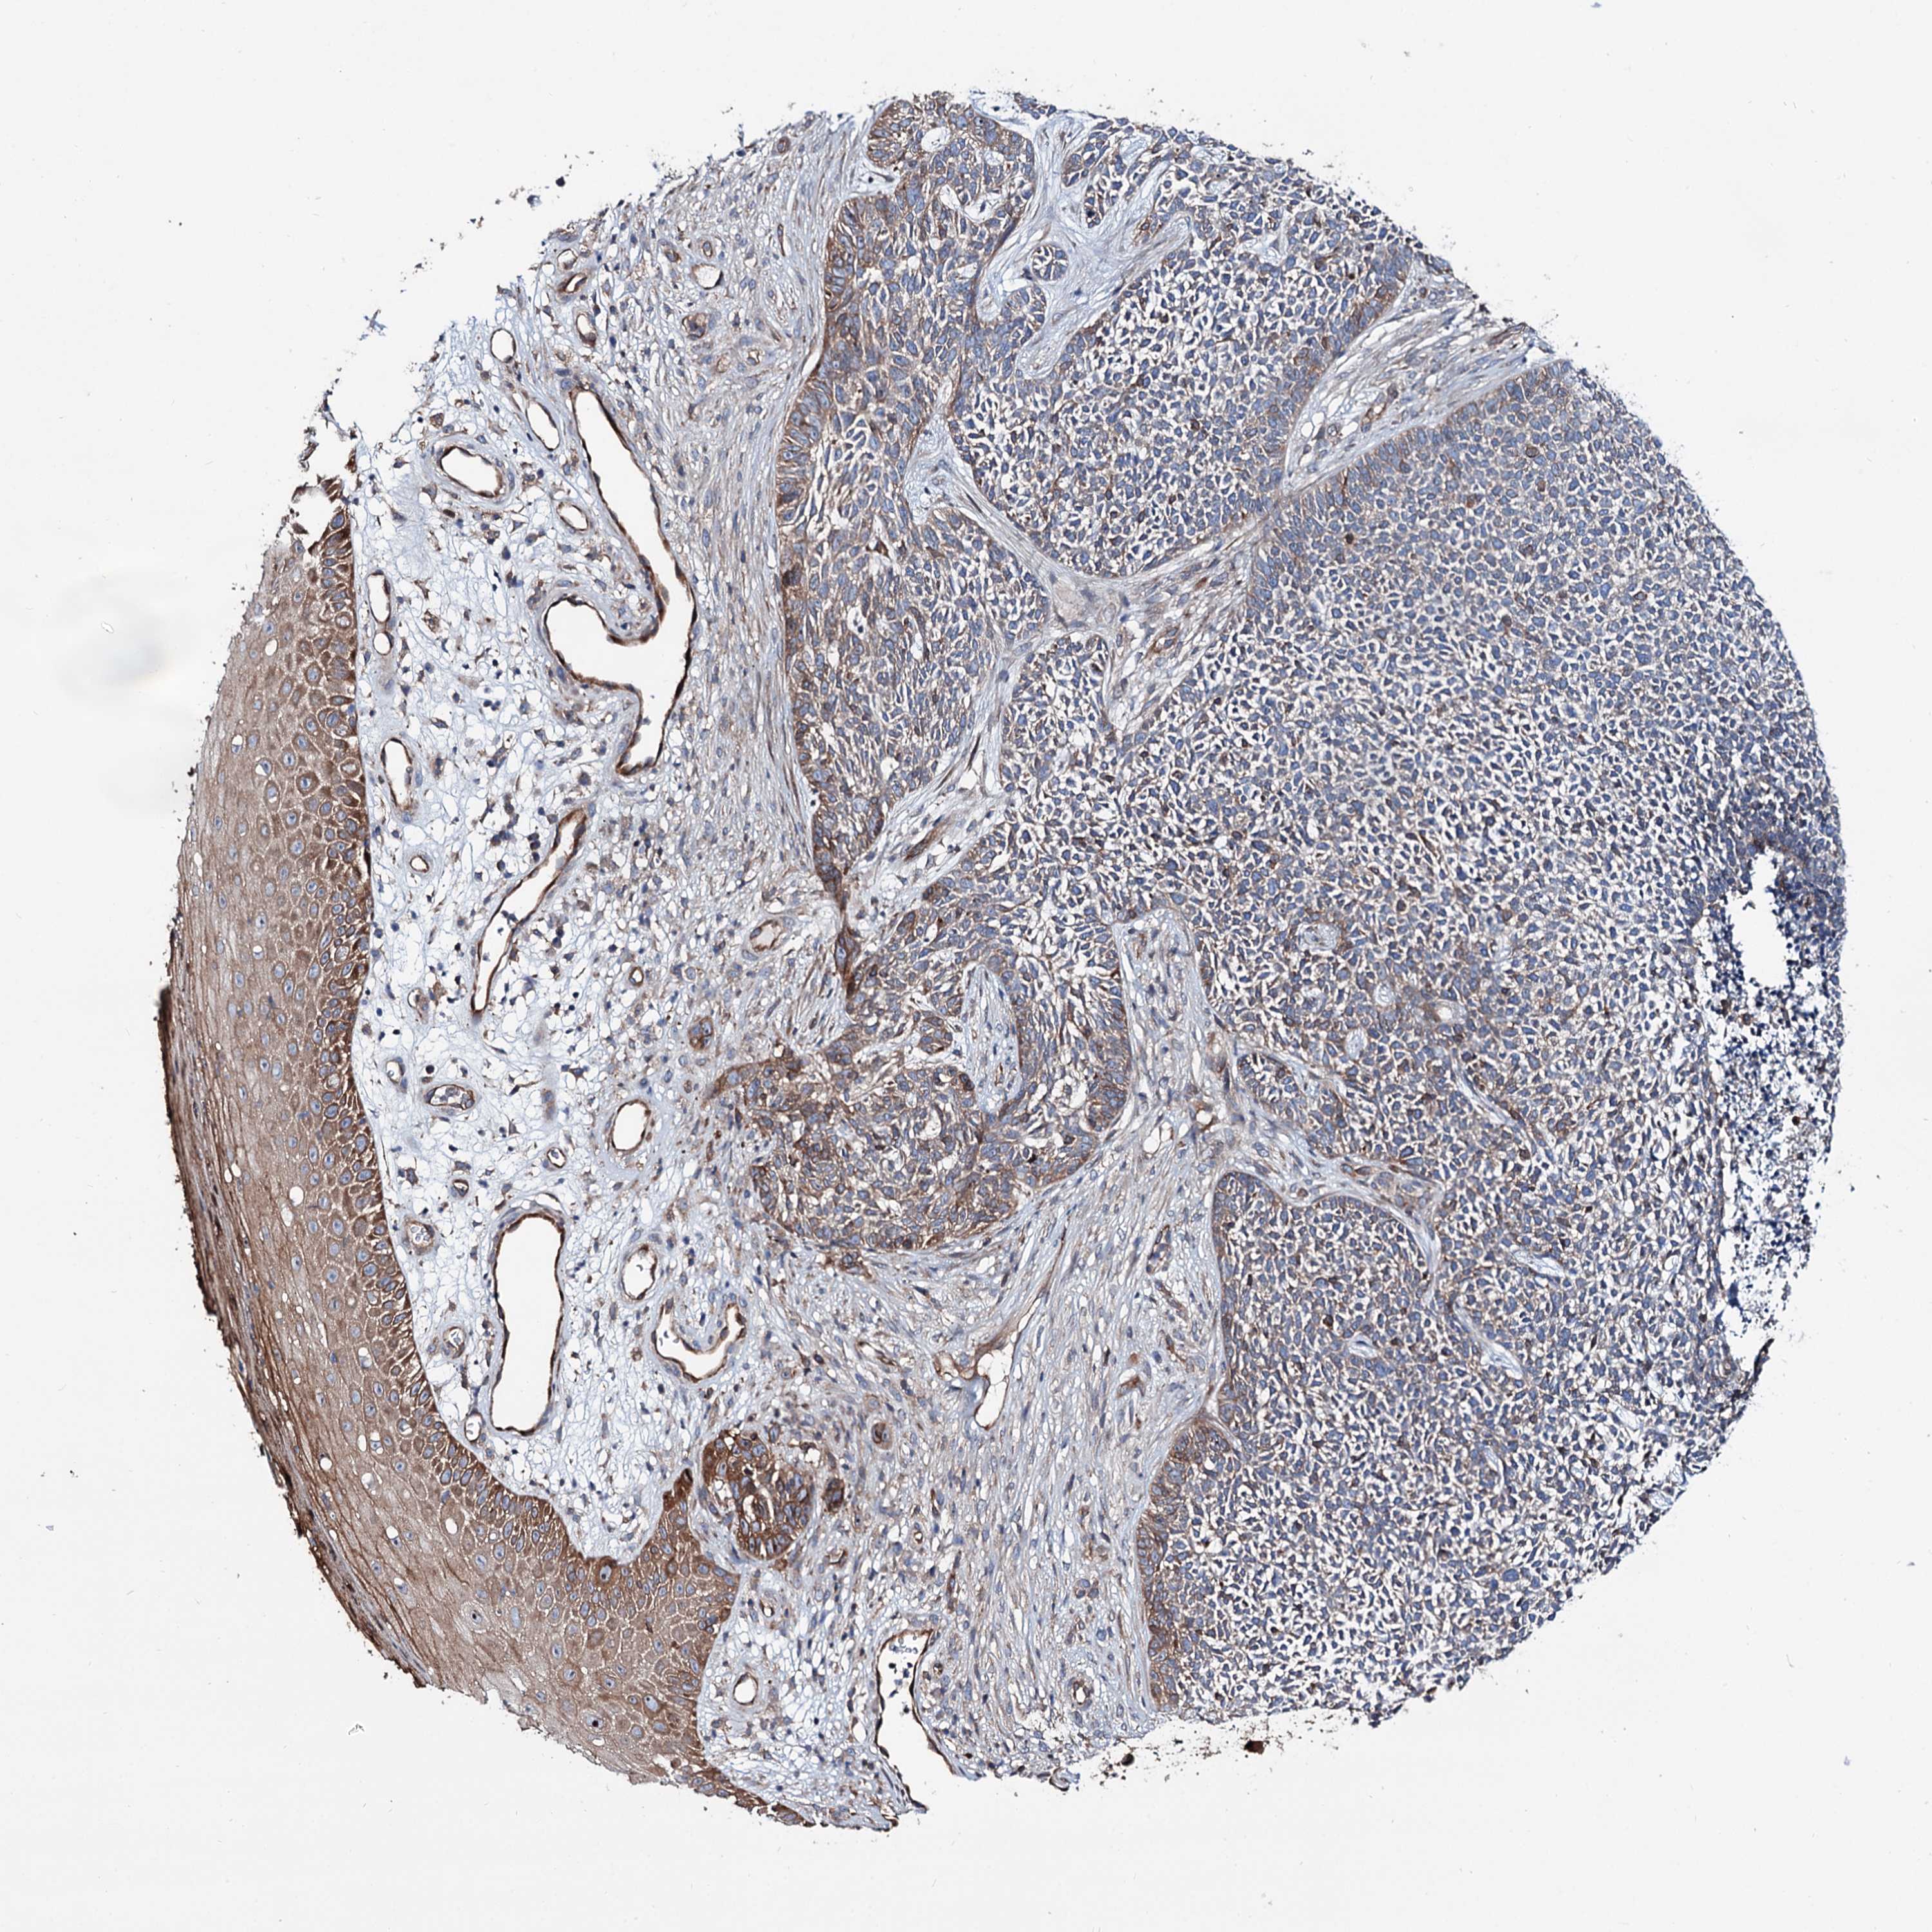

Basal cell and squamous cell cancer

SKIN CANCER - Protein expressioni

A mouse-over function shows sample information and annotation data. Click on an image to view it in a full screen mode. Samples can be filtered based on level of antibody staining by selecting one or several of the following categories: high, medium, low and not detected. The assay and annotation is described here.

Each image is clickable and will lead to virtual microscopy that enables deeper exploration of all samples and also displays staining intensity scores, fraction scores and subcellular localization as well as patient and tissue information for each sample.

Antibody HPA038928

Basal cell carcinoma